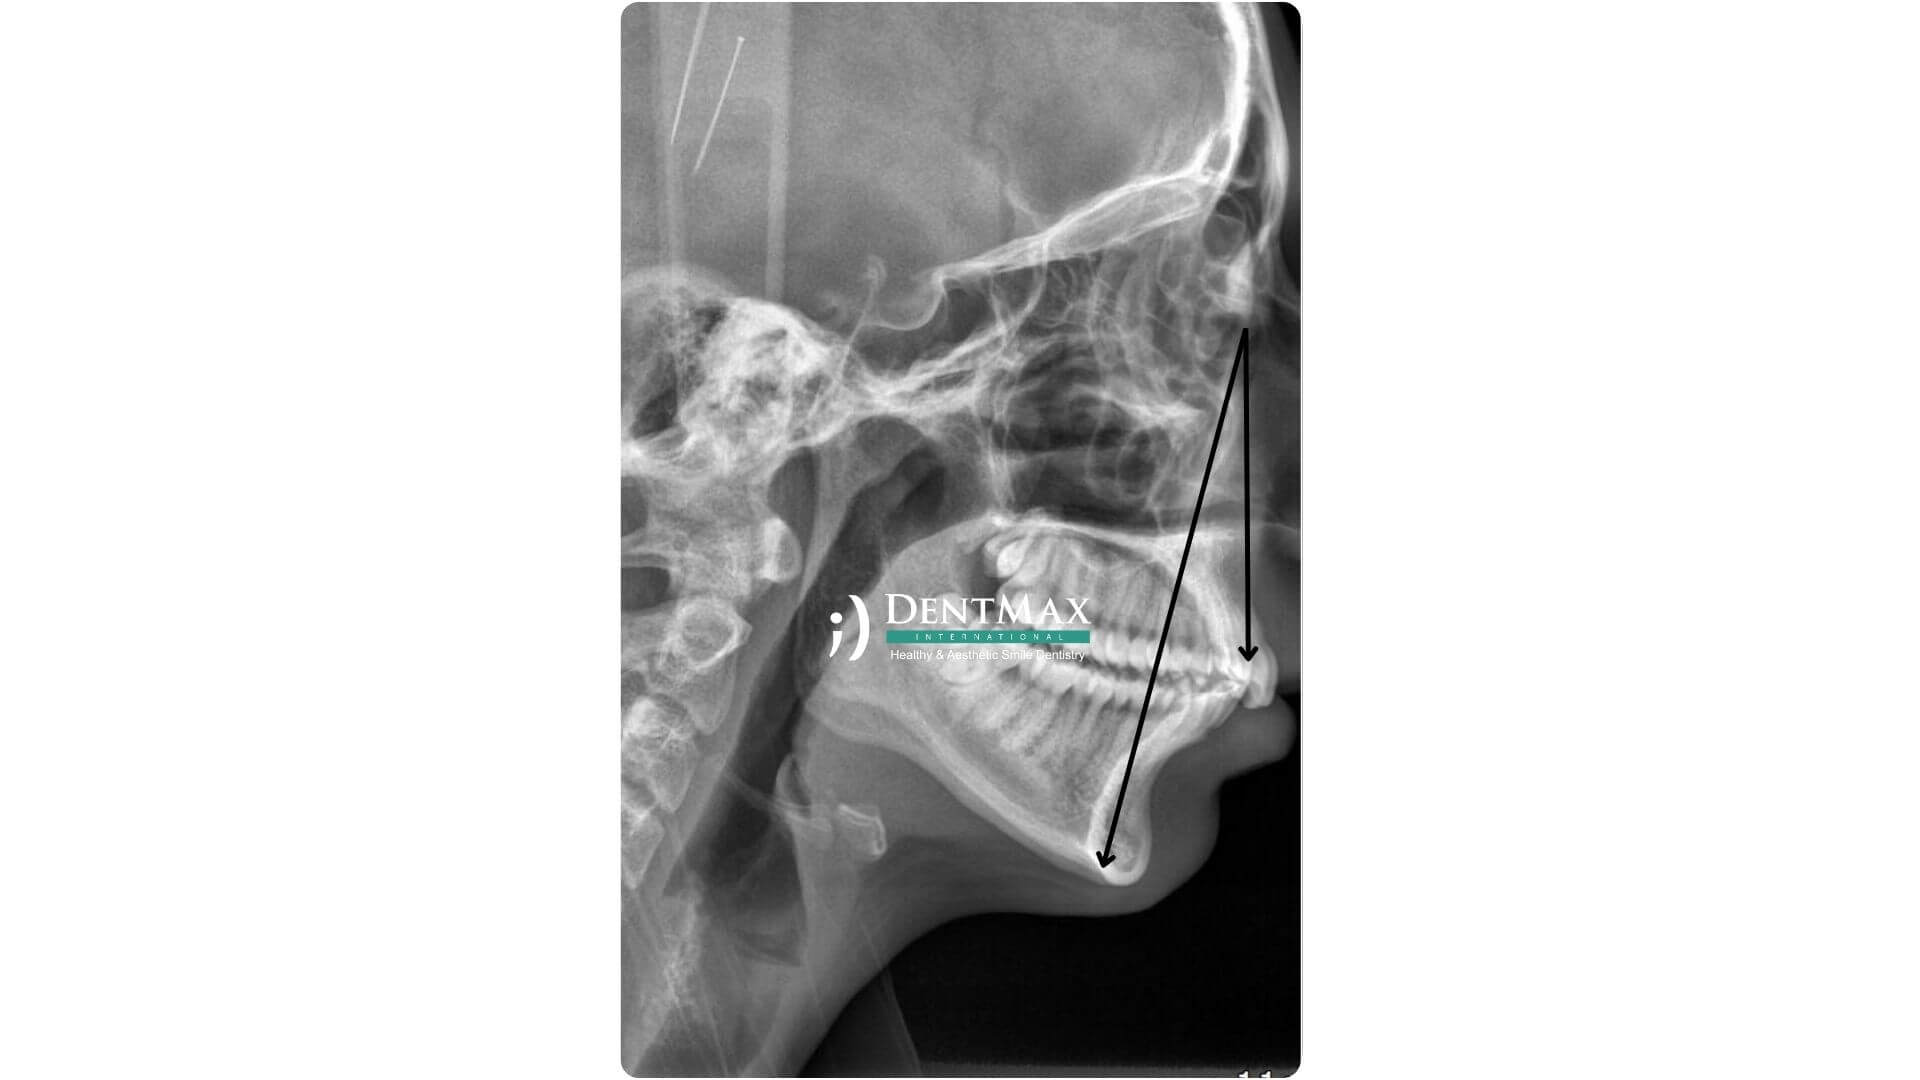

Qu’est-ce que la Rétrognathie Mandibulaire ?

C’est un décalage en arrière de la mâchoire inférieure par rapport à la mâchoire supérieure, affectant l’esthétique et la fonction.

Comment les Aligneurs Invisalign Corrigent-ils la Rétrognathie ?

Ils exercent une pression contrôlée pour repositionner les dents et la mâchoire vers l’avant. Le traitement est personnalisé.